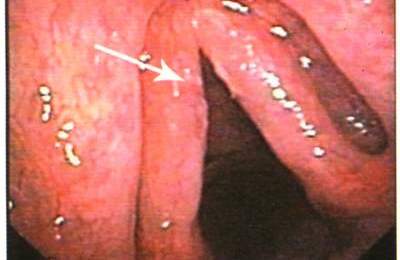

Хронический гиперпластический ларингит бывает двух типов: диффузный и ограниченный.

Диффузный тип проявляется равномерным отеком слизистых оболочек гортани, ограниченный – наличием в области голосовых связок симметричных бугорков соединительной ткани (так называемых «узелков певцов» или «узелков крикунов»).